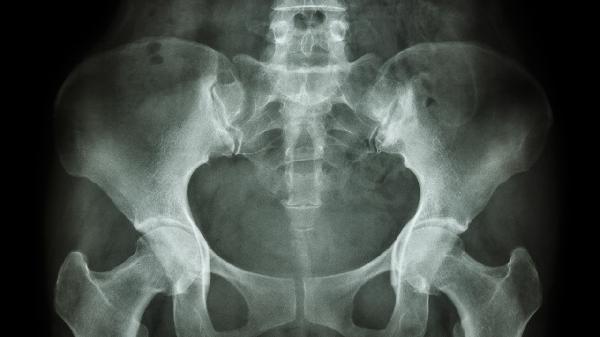

改善骨盆前倾的方法有哪些

改善骨盆前倾可通过调整姿势、加强核心肌群训练、拉伸髋部肌肉、使用辅助工具、手术治疗等方式干预。骨盆前倾通常由久坐、肌肉失衡、妊娠、腰椎病变、先天因素等原因引起。